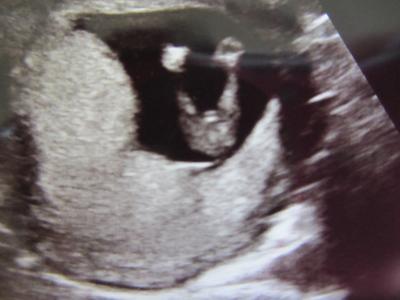

Hallo ihr Lieben!!! Ich war gestern beim FA. da war ich 13+2. Zwergi geht´s gut ist jetzt 6.8 cm "groß". Aufjedenfall hab ich ein tolles Bild bekommen, wo man die Beinchen (sieht aus wie ein V) und dazwischen ein kleines Schniedelchen sieht, zumindest meiner Meinung, auch der FA meinte: Ja das sieht eher aus wie ein Junge, aber das wäre noch zu früh um ein eindeutiges Ergebniss zu bestätigen, obwohl mein FA ein Top-USGerät hat (sichtbarer Herzsclag in der 6. SSW, 3D und 4D,er macht auch pränataldiagnostik usw.) Deshalb bitte ich Euch um Eure Meinung DANKE DANKE DANKE Also was sagt ihr, Junge oder Mädchen?????

Hallo! Auf dem Bild siehst du etwas das aussieht wie ein V, das sind die Beine und dazwischen, das ist eben die Frage: Junge oder Mädchen LG